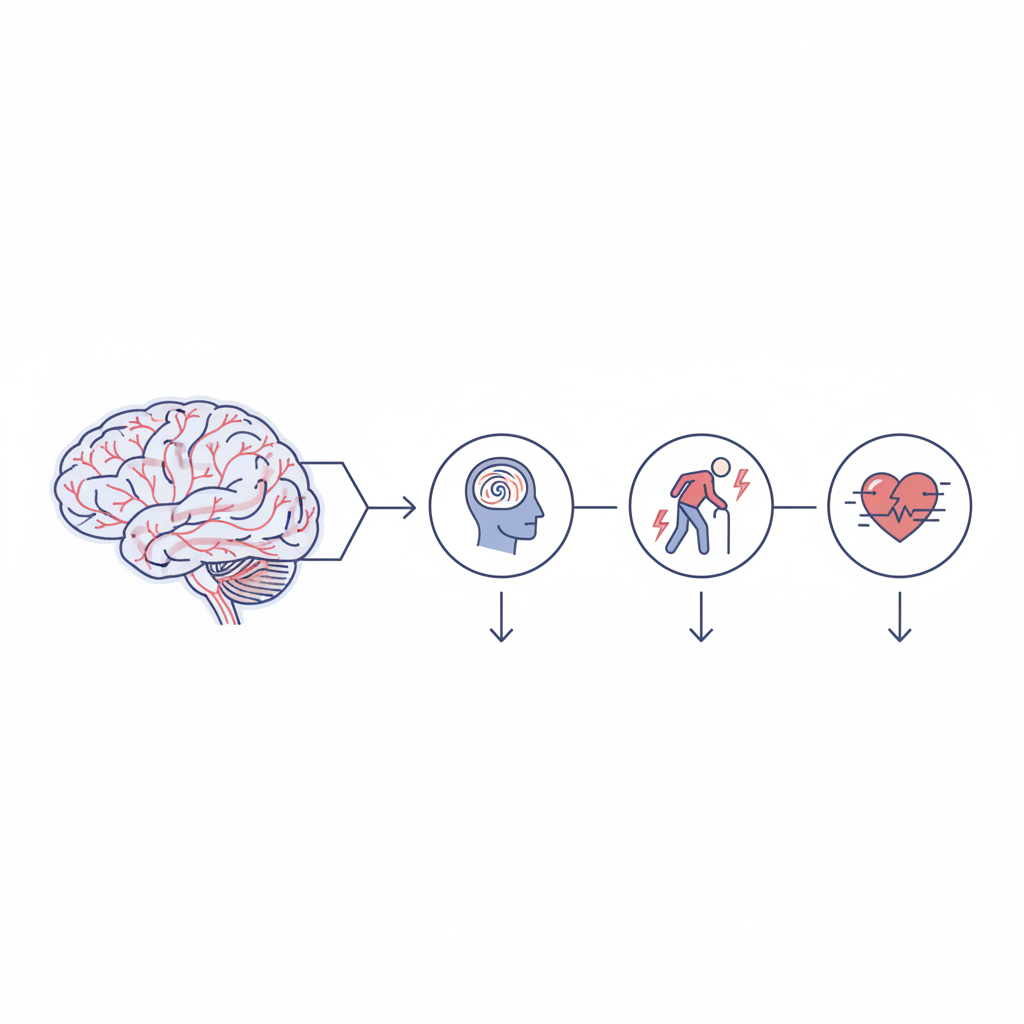

Церебральна мікроангіопатія — це ураження дрібних судин мозку, що живлять його найвразливіші ділянки білої та сірої речовини. Судинні стінки ущільнюються, просвіт звужується, мікроциркуляція слабшає. У тканинах мозку накопичується хронічний брак кисню та поживних речовин. Поступово виникають невеликі ділянки ушкодження, які на знімках МРТ виглядають як світлі плями у білій речовині або як маленькі «дірочки» — наслідки перенесених мікроінсультів. Хвороба розвивається тихо і роками. Але вплив на повсякденне життя може бути значним, бо страждають пам’ять, хода, рівновага, емоції та здатність планувати дії.

Це збірний термін для опису уражень капілярів, артеріол і венул мозку. Коли їхні стінки стають щільними і ламкими, доставка крові у критичні ділянки погіршується. Клітинам бракує кисню, і з’являються мікропошкодження. На МРТ це видно як ділянки зміни сигнала у білій речовині, дрібні порожнини від перенесених лакунарних інфарктів та крихітні крововиливи. Зміни розвиваються повільно, але їхній ефект накопичується. Так формується судинна когнітивна недостатність, порушення ходи, слабкість уваги і швидка втома після розумових навантажень.

Як проявляється церебральна мікроангіопатія

Початок нерідко непомітний. Людина списує усе на втому або вік. Змінюється швидкість мислення: складніше перемикати увагу, обробляти кілька завдань, утримувати деталі в пам’яті. Хода може стати повільною і менш впевненою, з’являється відчуття «прикутості» ніг до підлоги, хиткість на поворотах. Настрій коливається, з’являється тривога або пригніченість. У декого погіршується контроль сечовипускання, посилюється нічне вставання. Після стресу або інфекції симптоми стають помітнішими, бо мозку важче компенсувати дефіцит кровопостачання.

- Когнітивні зміни. Пам’ять на події та деталі, увага, планування, швидкість прийняття рішень. Це не обов’язково деменція, але сигнал про навантаження на мозок.

- Рухові порушення. Дрібні кроки, уповільнений старт руху, хиткість, інколи легкий тремор. Падіння стають імовірнішими.

- Емоції та поведінка. Дратівливість, апатія, зниження інтересу, проблеми зі сном. Депресія частіше має судинний компонент у старшому віці.

До чого може призвести

Найпоширеніші наслідки — лакунарні інсульти, що дають осередкові симптоми: слабкість в руці або нозі, порушення мови, оніміння половини обличчя. Інколи ці симптоми зникають, але на МРТ лишаються «лакуни», які з часом накопичуються. Можливі мікрокрововиливи, що погіршують рівновагу і мислення, а при амілоїдній ангіопатії — і великі крововиливи у корі мозку. Довготривалий перебіг без контролю факторів ризику веде до судинної деменції, коли страждають повсякденні навички: управління фінансами, прийом ліків, маршрути у місті, приготування їжі. Одночасно збільшується потреба у сторонній допомозі, зростає ризик падінь і травм, приєднуються хронічні болі та тривога.